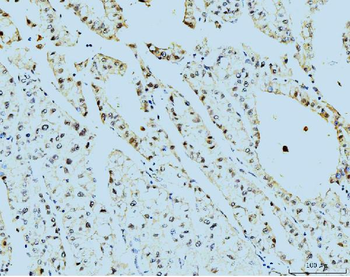

IHC analysis of TBP-1/PSMC3 using anti-TBP-1/PSMC3 antibody. TBP-1/PSMC3 was detected in paraffin-embedded section of human pancreatic cancer tissue. Heat mediated antigen retrieval was performed in EDTA buffer (pH8.0, epitope retrieval solution). The tissue section was blocked with 10% goat serum. The tissue section was then incubated with 2 µg/ml rabbit anti-TBP-1/PSMC3 Antibody overnight at 4°C. Biotinylated goat anti-rabbit IgG was used as secondary antibody and incubated for 30 minutes at 37°C. The tissue section was developed using Strepavidin-Biotin-Complex (SABC) with DAB as the chromogen.